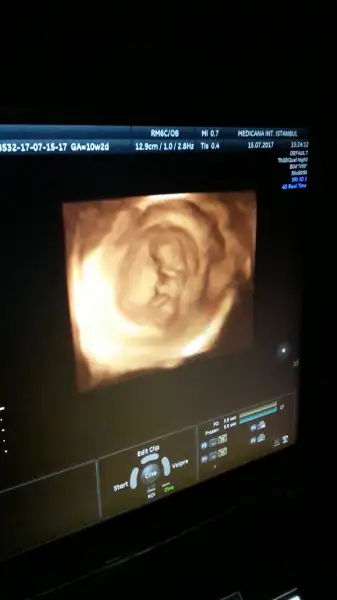

Maşallah Canım Bence bu bi erkeekkKızlar biz geldik herşey süper çıktı Allah'a şükür.. darısı sizlere bizimki elini ağzına götürüp duruyordu :)) cinsiyeti sordum şimdilik erken diye bişey demedi doktor tahminlerinizi alalım teyzeler sizce ne :)